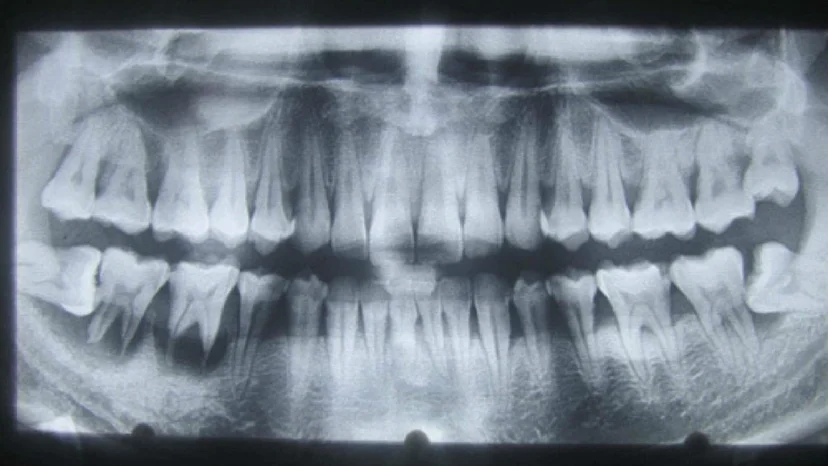

Chụp X quang răng là phương pháp sử dụng tia X để ghi lại hình ảnh cấu trúc bên trong răng, xương hàm và các mô quanh răng mà mắt thường không thể quan sát được. Đây là công cụ quan trọng giúp bác sĩ nha khoa phát hiện sớm các vấn đề như sâu răng, răng mọc lệch, viêm tủy, viêm nha chu, răng khôn, u nang hoặc tổn thương xương hàm. Chụp X quang có thể thực hiện với một răng, nhiều răng, hoặc toàn bộ hàm, tùy theo mục đích chẩn đoán và điều trị.

3.3. X quang toàn hàm (Panorama/Panorex)

– Ghi lại hình ảnh toàn bộ hai hàm răng, xương hàm, khớp thái dương hàm trên một phim.

– Dùng để kiểm tra răng khôn, mọc lệch, nang – u xương hàm, theo dõi niềng răng, cấy implant…